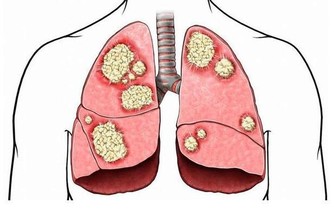

五、可以降低血脂下蹲運動通過刺激經絡系統,可使脾經運化功能增強,促進血管壁粥樣斑塊的分解,

降低血液的粘稠度,減少血液中甘油三酯和低密度脂蛋白,增加高密度脂蛋白,促進脂代謝,

進而改善血管的彈性,有效防治動脈粥樣硬化,對預防心、腦血管意外的發生有重要意義。